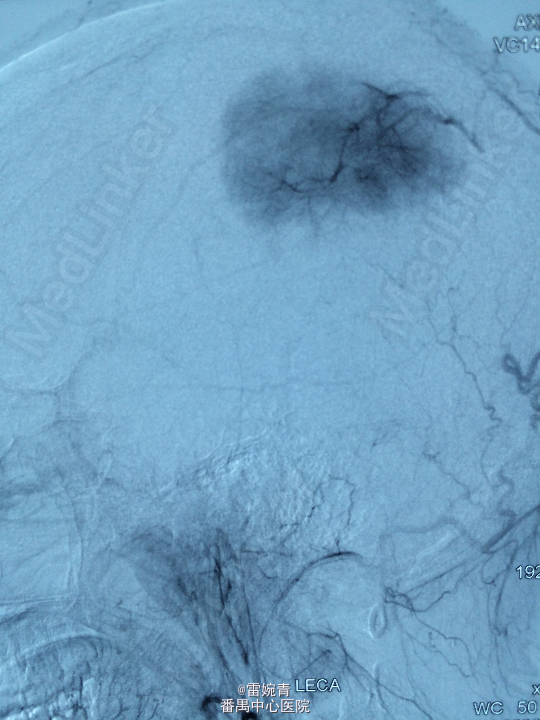

诊断:脑膜瘤 处理:先行DSA检查以明确脑膜瘤的供血动脉情况,见:肿瘤染色,肿瘤主要由左侧眼动脉供血,用Glubran胶将其闭塞,后择期行手术切除治疗。术后病理证实为脑膜瘤。